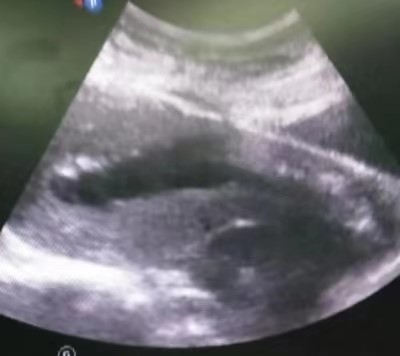

34岁的欧女士来自安仁县,因“停经55天,阴道流血4天,发现切口妊娠2天”于8月22日由门诊以“切口妊娠”收住入院。B超检查提示,剖腹产切口处15x14x11mm孕囊,内见卵黄囊,距离子宫浆膜层4mm,血流丰富。考虑切口妊娠。MRI提示:子宫中段前壁见切口凹陷,有26x15mm大小孕囊附着,附着处16mm肌层变薄,最薄处4mm,子宫前壁与腹壁粘连。诊断:子宫切口妊娠,子宫前壁与腹壁粘连。

超声像                                       MRI影像